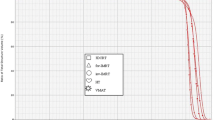

All treatment plans were evaluated according to the dose-volume histogram. The evaluated dosimetric parameters for PTVs were the volume of PTV receiving 95% of the prescribed dose (V95%), volume of PTV receiving > 107% but < 110% of the prescribed dose (V > 107%), dose received by 2% of the PTV (D2), dose received by 98% of the PTV (D98), dose received by 50% of the PTV (D50), conformity index (CI), and homogeneity index (HI). The total MUs of all treatment plans were also compared. For OARs, the evaluated dosimetric parameters were the volume receiving ≥ 40 Gy of the prescribed dose (V40) for bone marrow, volume receiving ≥ 45 Gy of the prescribed dose (V45) for the bladder, volume receiving ≥ 30 Gy of the prescribed dose (V30) for the rectum, volume receiving ≥ 35 Gy and ≥ 40 Gy of the prescribed dose (V35 and V40) for the bowel, and volume receiving ≥ 30 Gy of the prescribed dose (V30) for the femurs. Accepted dose constraints for OARs according to the literature are shown in Table 2 [6, 18, 19]. Because this was a dosimetric study, we did not compromise PTV coverage, even when OARs would be exposed to doses that exceeded the dose constraints.

Dosimetric results obtained with dose-volume histograms of PTV, OARs, and NT were obtained from 60 treatment plans; three different plans were analyzed for each of the 20 patients. The volumes of the PTV and OARs in milliliters (ml) are shown in Table 3.